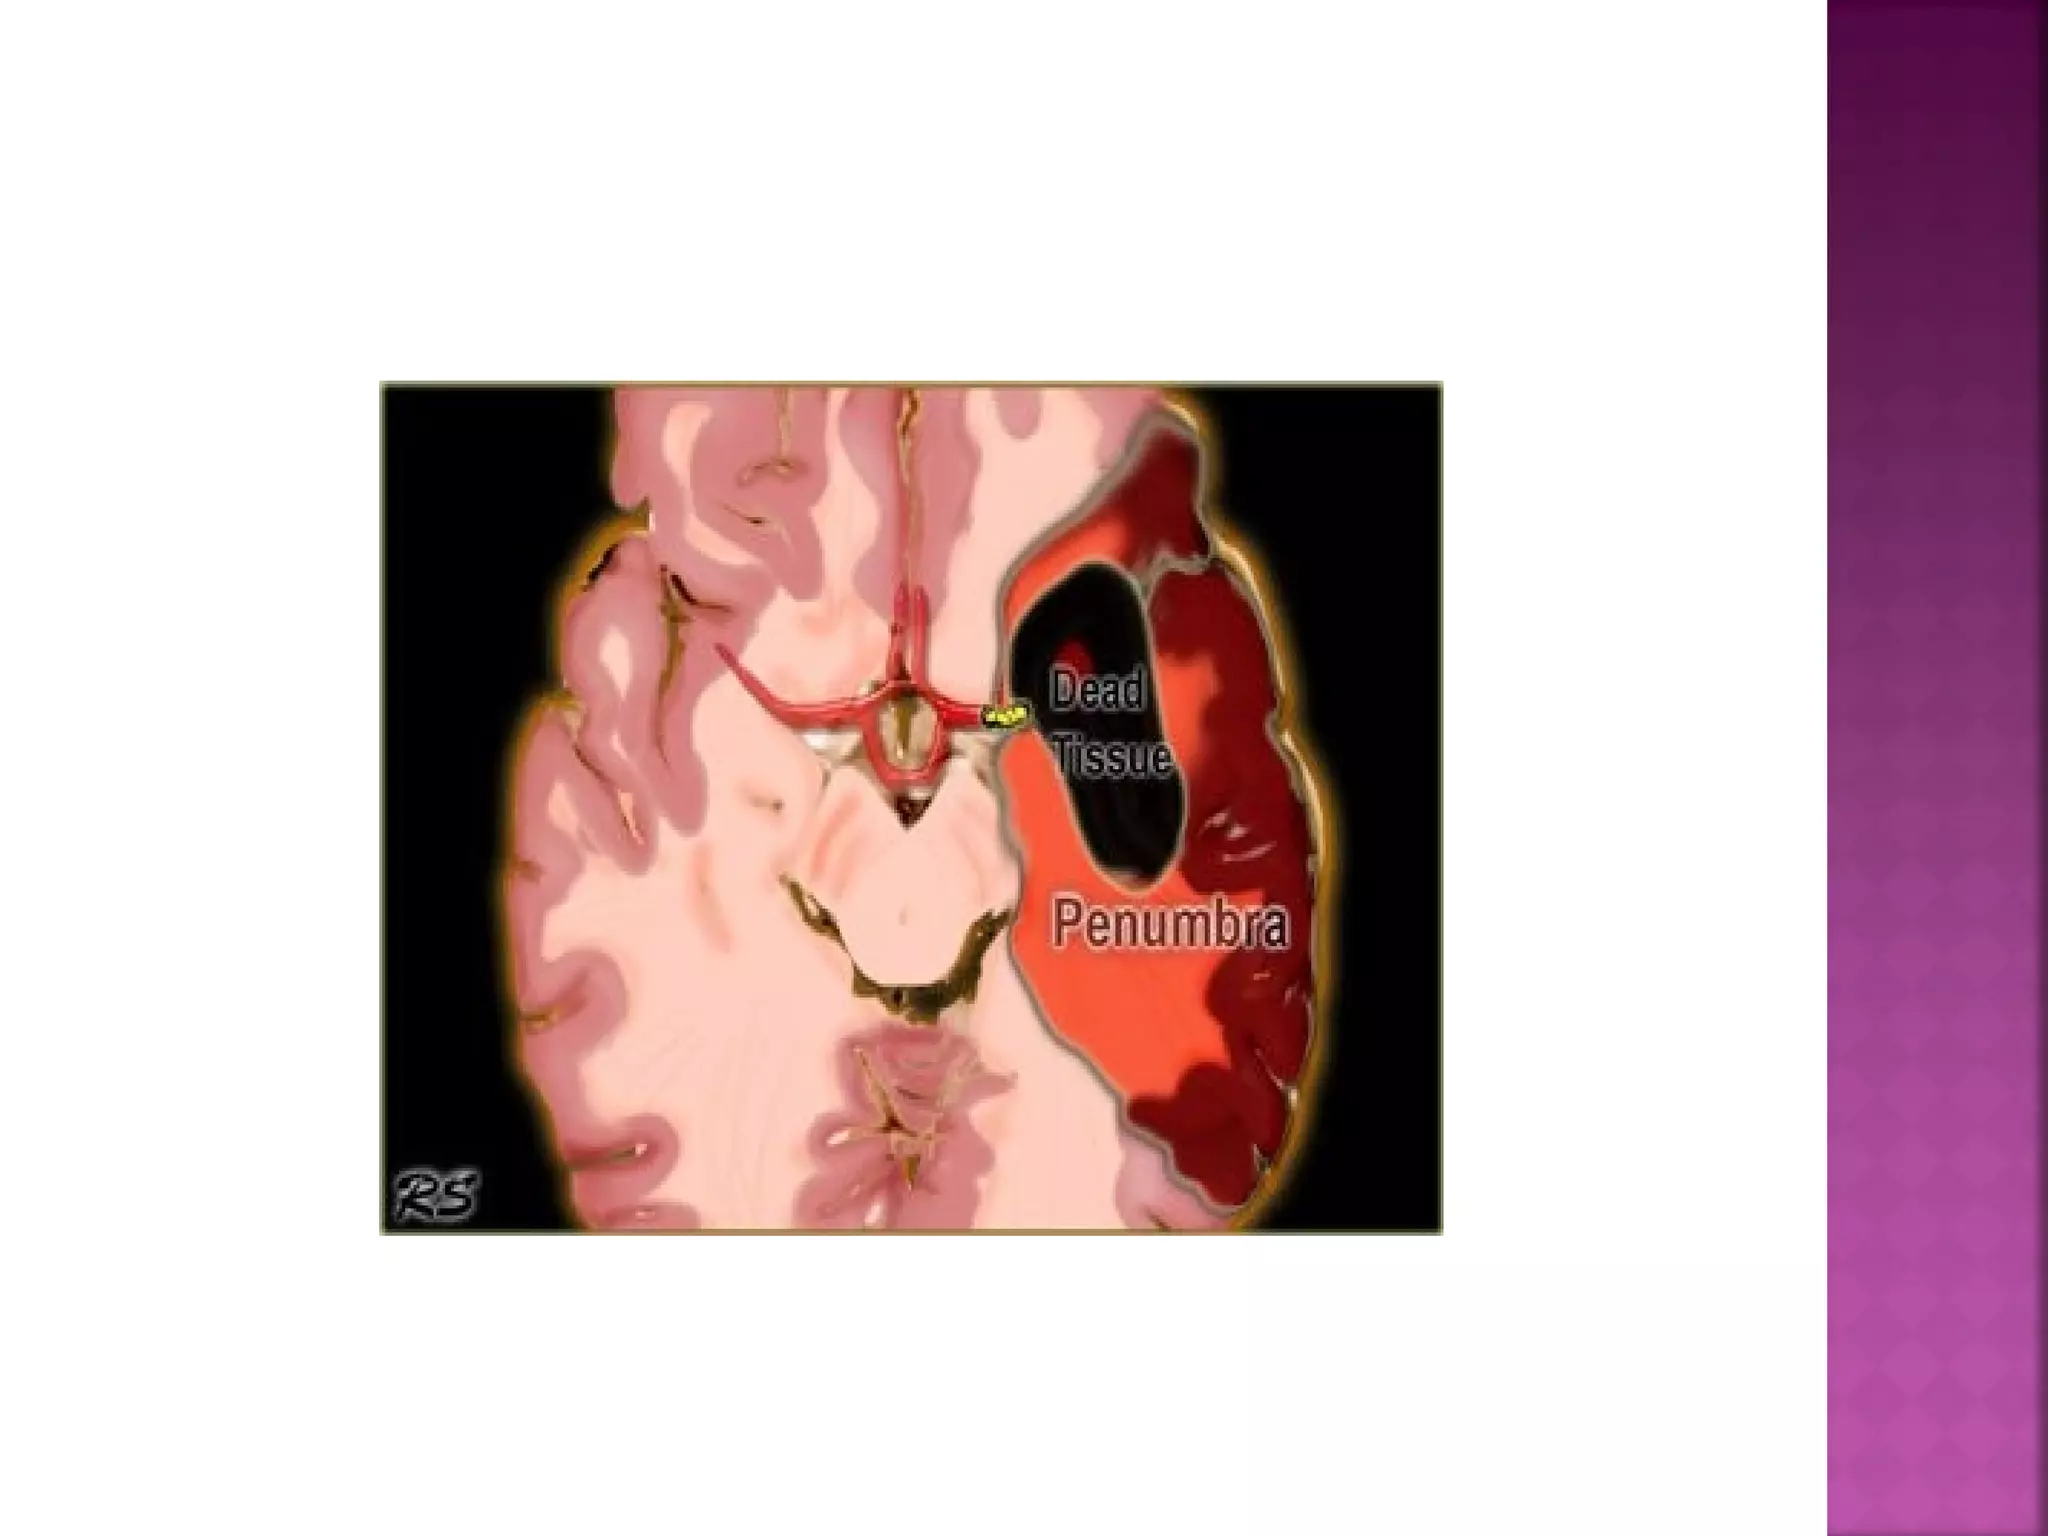

 Differentiate between irreversibly affected

brain tissue and reversibly impaired tissue

(dead tissue versus tissue at risk)

The goal ofimaging in a patient with acute stroke is:  Exclude hemorrhage  Differentiate between irreversibly affected brain tissue and reversibly impaired tissue (dead tissue versus tissue at risk)  Identify stenosis or occlusion of major extraand intracranial arteries